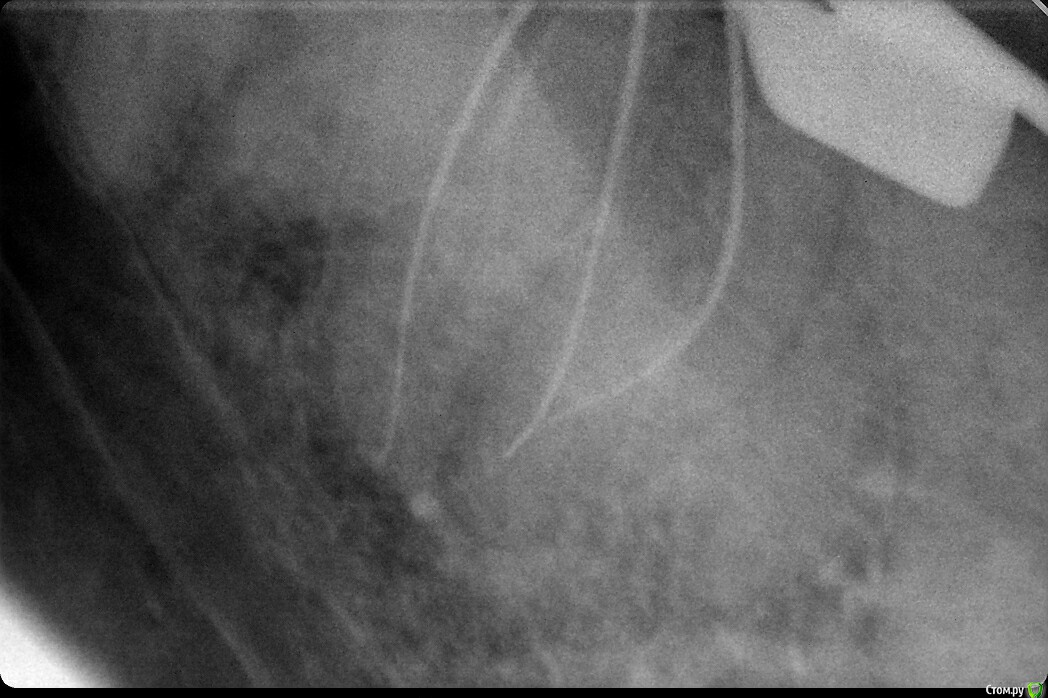

Antanta Опубликовано 25 ноября, 2018 Поделиться Опубликовано 25 ноября, 2018 Добрый вечер. Сделала огромную ошибку. Такие длинные корни и такой короткий штифт в дистальном канале получился. Вкладка сделана непрямым методом. С техником решили не делать штифты в медиальные каналы, пришлось заполнить цементом. Зуб сейчас под временной коронкой, планируется в ближайшее время изготовить металлокерамическую коронку. Но я мучаюсь и не могу решить, выпилить и переделать вкладку, сделать в дистальном канале штифт длиннее. Или оставить как есть, запротезировать и ждать..будет ли перелом дистального корня? Феррул у зуба есть, была своя щечная стенка, остальная часть зуба была восстановлена композитом, язычная стенка разрушена до десны, медиальная и дистальная чуть выше десны. Пожалуйста, помогите советом Ссылка на комментарий

Doc Опубликовано 26 ноября, 2018 Поделиться Опубликовано 26 ноября, 2018 Добрый вечер. Сделала огромную ошибку. Такие длинные корни и такой короткий штифт в дистальном канале получился. Вкладка сделана непрямым методом. С техником решили не делать штифты в медиальные каналы, пришлось заполнить цементом. Зуб сейчас под временной коронкой, планируется в ближайшее время изготовить металлокерамическую коронку. Но я мучаюсь и не могу решить, выпилить и переделать вкладку, сделать в дистальном канале штифт длиннее. Или оставить как есть, запротезировать и ждать..будет ли перелом дистального корня? Феррул у зуба есть, была своя щечная стенка, остальная часть зуба была восстановлена композитом, язычная стенка разрушена до десны, медиальная и дистальная чуть выше десны. Пожалуйста, помогите советомНу, конечно же дистальный мог быть в два раза длиннее, а медиальные легко могли быть длиной с дистальную ножку, какая она есть сейчас. Но выпиливать из-за этого вкладку уж точно нет смысла. Вреда можете нанести больше, чем если так оставить. При наличии нормального ферула и качественного прилегания коронки оно еще сто лет простоит! Начнете выпиливать, так может и треснуть, и перегреться, и лишних тканей спилите. Так что не заморачивайтесь, так сойдет. На будущее просто учтите. 4 Ссылка на комментарий